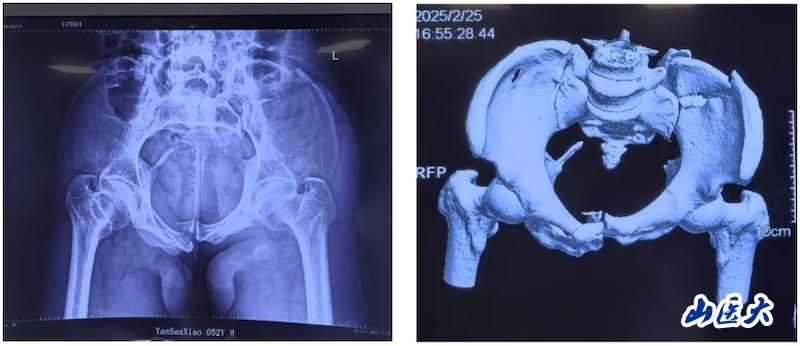

術前

該患者在駕駛三輪車時發生車禍,導致骨盆骨折,經過當地醫院對癥治療后轉入我校第二醫院急診科。由于血色素持續下降,血管外科首先進行了血管介入栓塞處理,隨后轉入骨科創傷病區,由孫海鈺團隊接續治療。經過詳細檢查和評估,孫海鈺主任、賀冬冬副主任醫師、王歡副主任醫師為患者制定了運用UCRT解鎖復位技術,結合天璣機器人及O-arm術中影像系統為其實施骨盆閉合復位的手術治療方案。3月6日,孫海鈺團隊在骨科老一輩專家尹蕓生主任的指導及麻醉師、技師、器械護士和巡回護士的通力協助下,成功運用微創新技術為患者實施了手術。